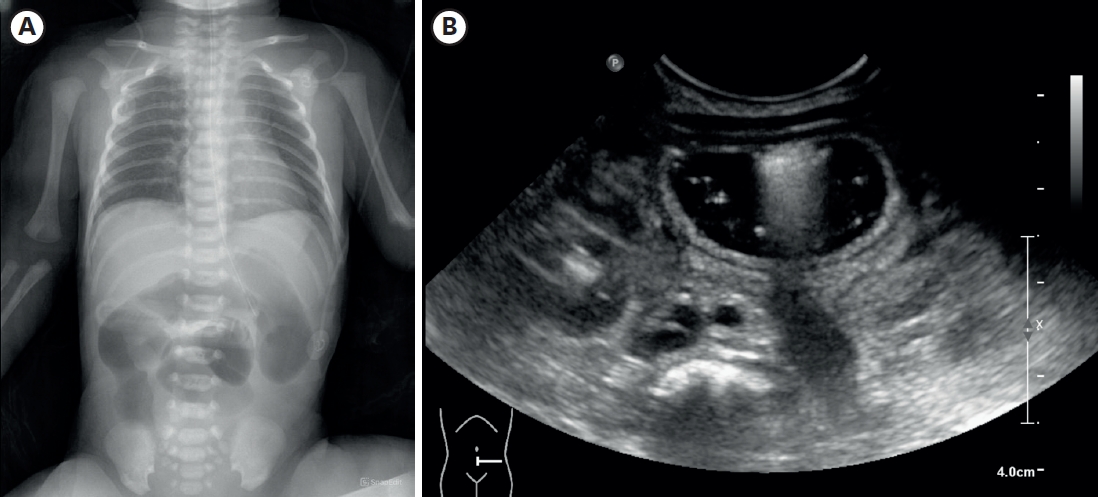

Hirschsprung Disease Associated With Pelvic Neuroblastoma: A Rare Neurocristopathic Association

Sravanthi Vutukuru, Nitin J Peters, Shailesh Solanki, Amita Trehan, Kirti Gupta, Monika Bawa

Adv Pediatr Surg 2024;30(1):32-37.   Published online January 29, 2024

DOI: https://doi.org/10.13029/aps.2024.30.1.32

Hirschsprung disease (HSCR) is a genetic disorder with an incidence of 1:5000, seen in the pediatric age group. The association between HSCR and neuroblastoma (NBL), ends of the neurocristopathy spectrum is rare. Less than 10 cases of this association are reported in the literature and the association between the Phox gene and Sox10 gene in the pathophysiology of these is being studied. We report a one-year-old baby, who presented to us, with chronic constipation on regular enemas and laxative usage. There was a history of delayed passage of meconium. At the time of Duhamel’s pull through a well-defined, bilobed hard presacral mass, was encountered. Excision and coccygectomy were done and the pull was completed. The histopathology showed a well-differentiated NBL. Fludeoxyglucose positron emission tomography scan and the N-Myc amplification were negative and the patient was managed with expectant treatment. She is doing well over a 3-year follow-up with no recurrence and good resolution of bowel functions.